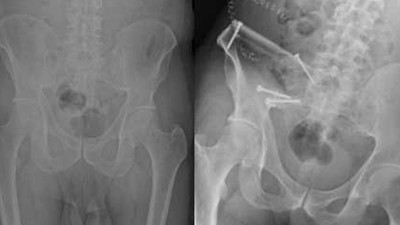

Prostat kanserinin ileri evrelerindeki kemik tehlikesiyle uzman önerileri Prostat kanserinin ileri evrelerinde görülen kemik metastazları, iskelet sisteminde geri dönülemez hasarlara ve ani kırılmalara yol açtı. Uzmanlar, geçmeyen eklem ağrılarının kanserin yayılma belirtisi olabileceği konusunda kritik uyarılarda bulundu.